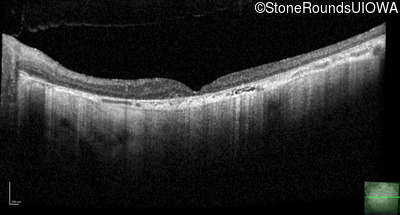

Optical Coherence Tomography - Right - 10/200

Exemplar / OCT Stack